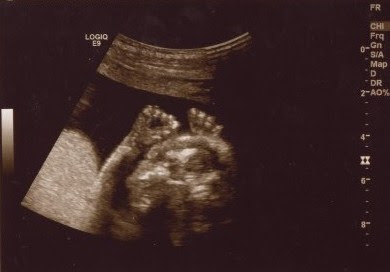

For an hour and a half today we watched, smiled, and cried at the images of our sweet baby boy. I learned a new kind of love today and my heart is full. I can't get enough of his little profile. We are so very blessed. Meet our little guy: